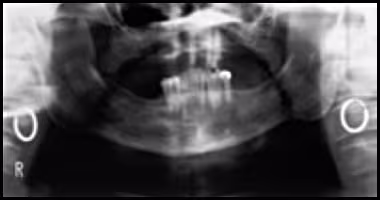

These figures demonstrate the visual effects on the image when the patient’s head is too far forward during exposure: spine superimposes over the ramus area, nasal fossa and maxillary sinus become clearly evident, and the anterior teeth are narrowed and blurred.

Figure 51A. Panoramic Image.

Figure 51B. Panoramic Schematic.